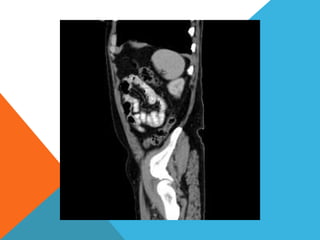

El paciente presentó síntomas de sangrado digestivo y pérdida de peso. Exámenes revelaron gastritis crónica asociada a H. pylori. Un tumor fue descubierto en una colonoscopia normal. La cirugía removió un tumor fibroide solitario, una rara neoplasia mesenquimal que usualmente crece lento y tiene bajo potencial de malignidad. El pronóstico después de la remoción quirúrgica es generalmente bueno.